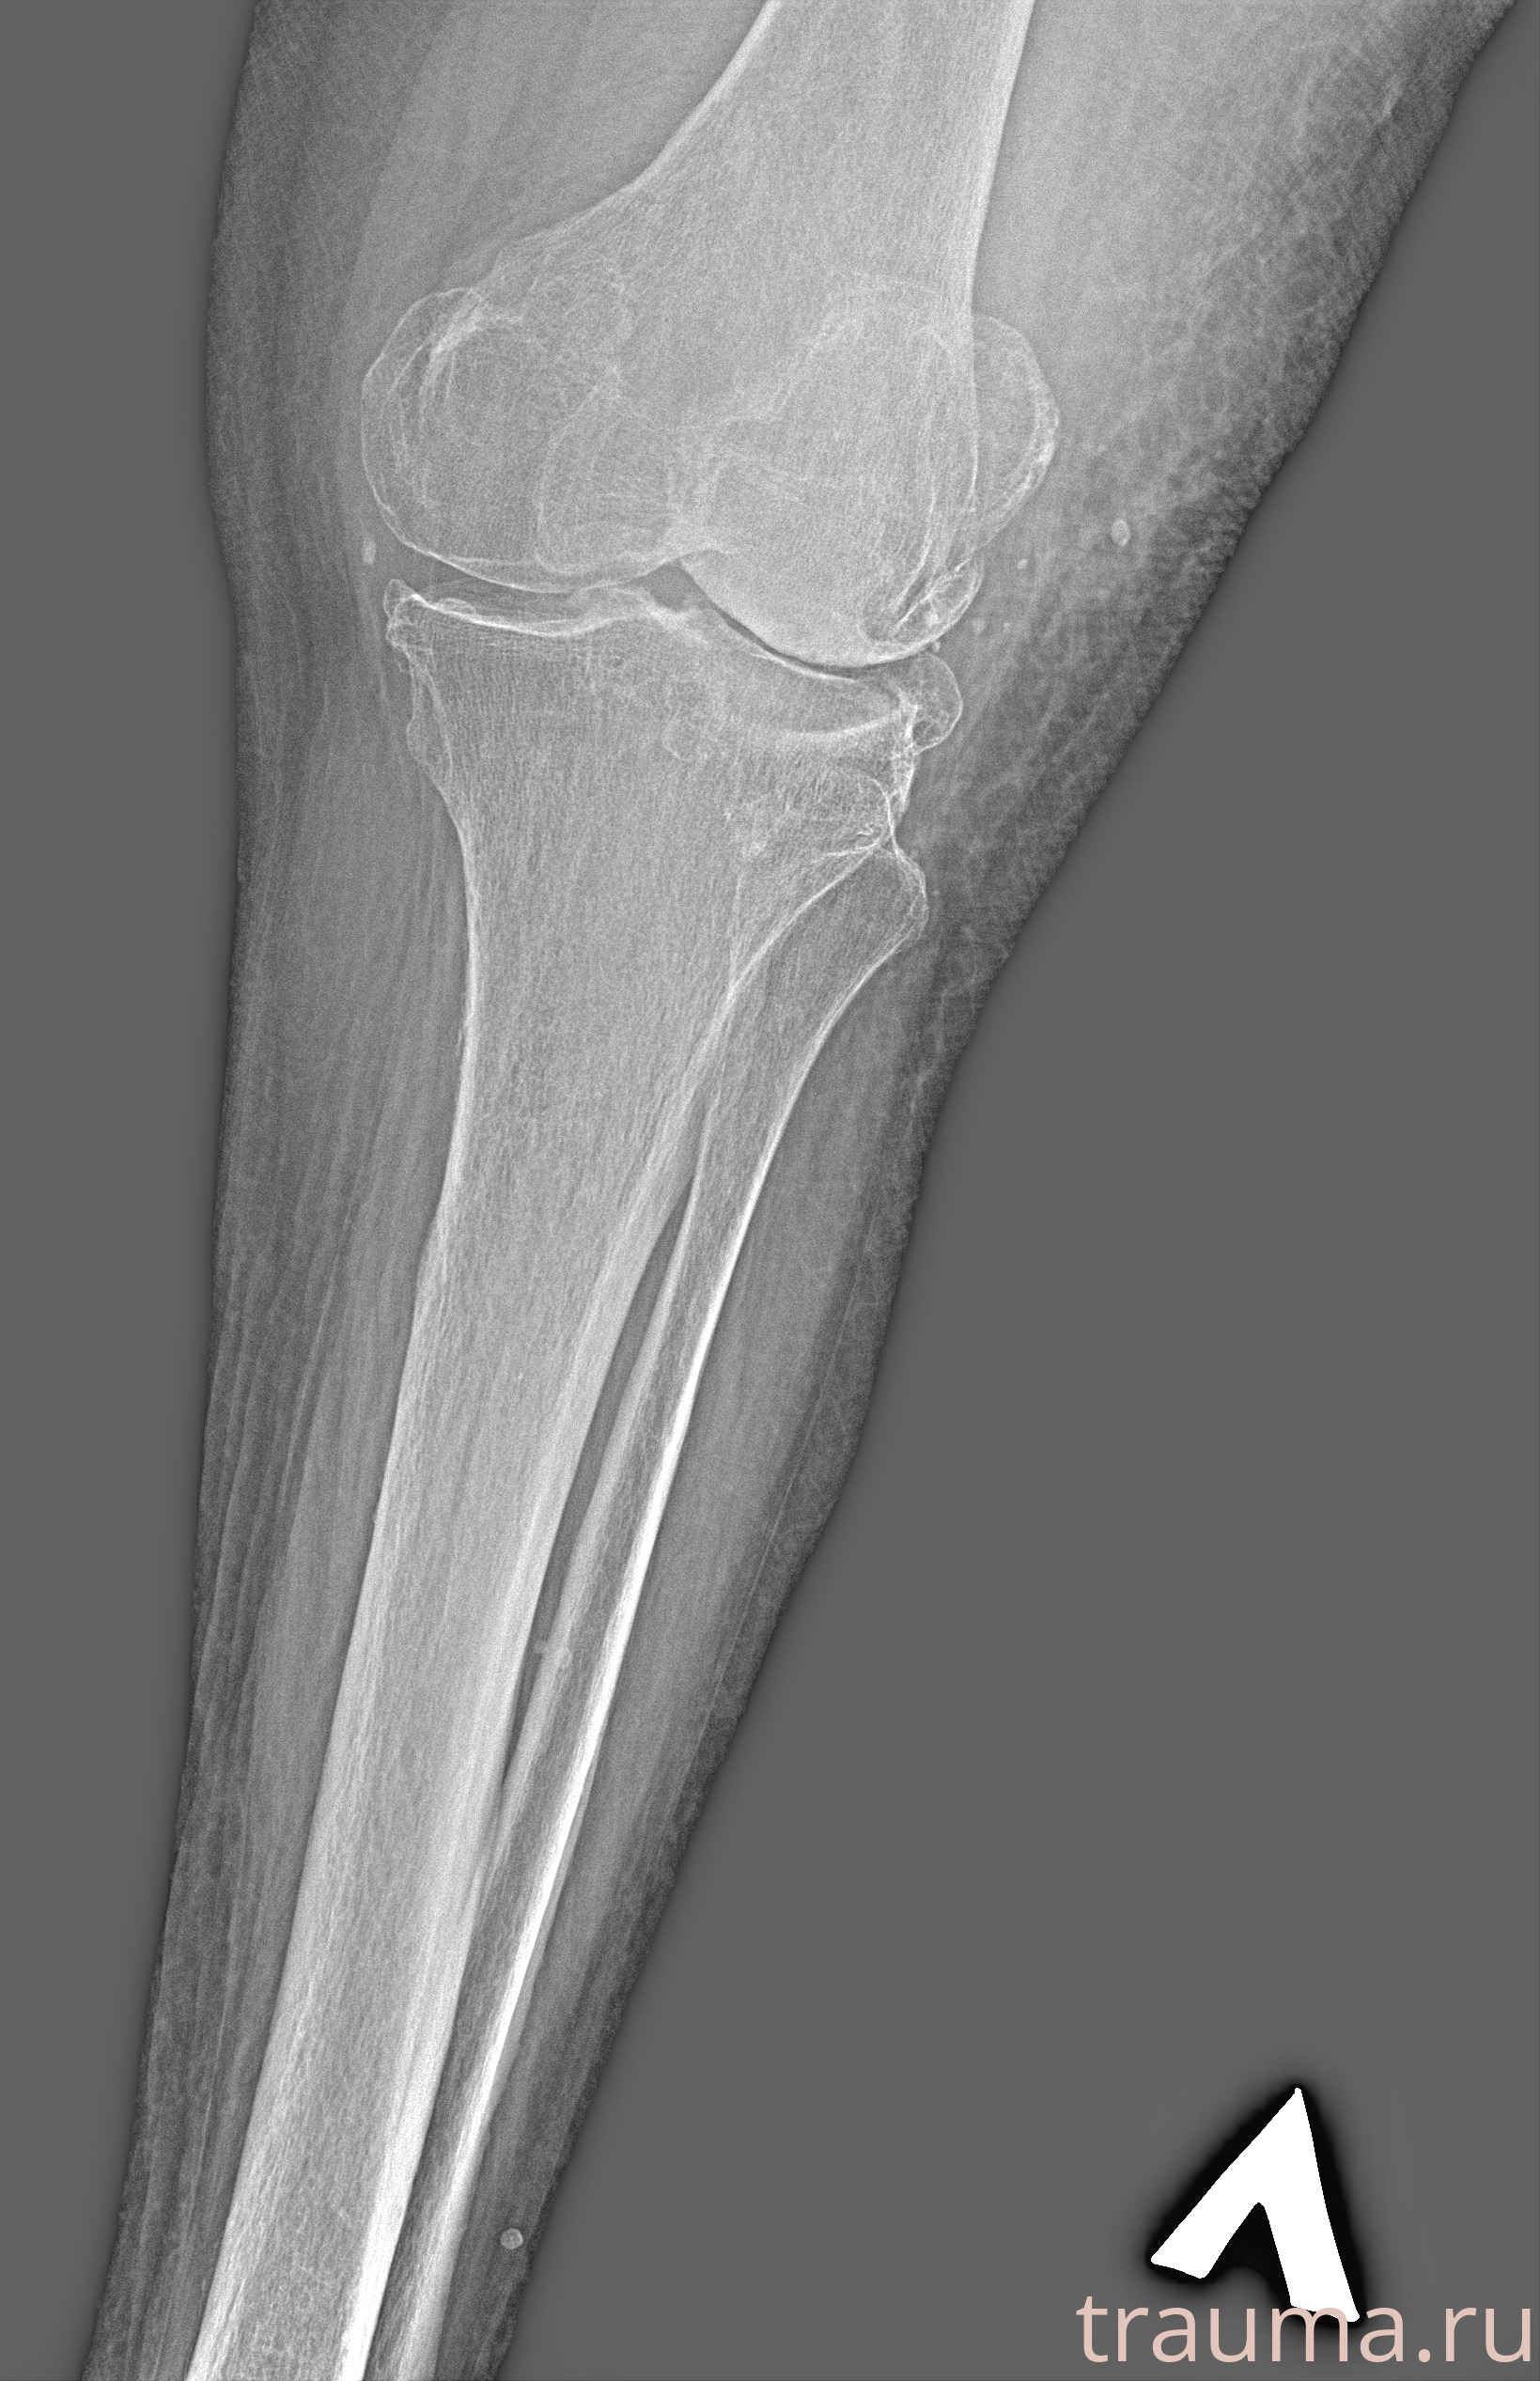

Рентгенограммы

Рентген на дому: по вашему адресу приезжает врач-рентгенолог, травматолог-ортопед с мобильным рентгеновским аппаратом, проводит диагностику травмы или заболевания, делает необходимые рентгенограммы, дает рекомендации по дальнейшему лечению. Получить качественные снимки в домашних условиях возможно благодаря уникальной методике, разработанной МосРентген Центром для института  Склифосовского